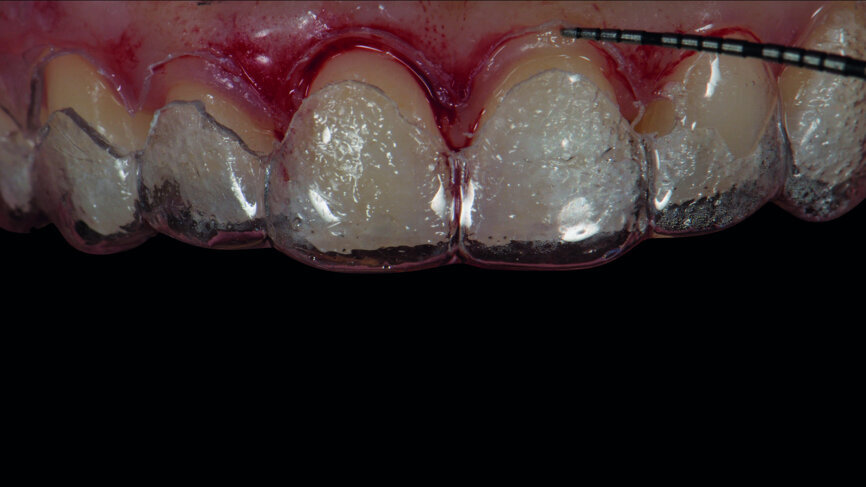

Figs. 6a: Intraoral fi t of the surgical guide for crown lengthening.

Figs. 6b: Intraoral fi t of the surgical guide for crown lengthening.